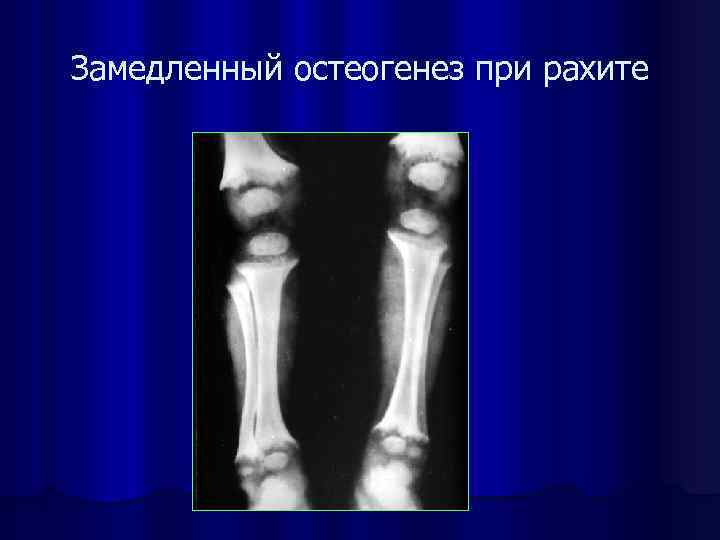

Замедленный остеогенез при рахите